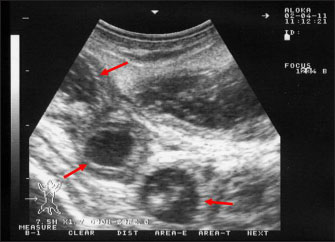

Ultrasonography has been proven effective for the early detection of several abdominal and thoracic disorders in small ruminants (Tharwat et al., 2012b; Tharwat and Al-Sobayil, 2017; Tharwat, 2021; Sadan et al., 2023; Tharwat and Al-Hawas, 2024a,b; Tharwat et al., 2024; Tharwat et al., 2025b). Recently, the technique has been found valuable for the diagnosis of various bacterial and parasitic infections in ruminants (Tharwat and Tsuka, 2024). An overall increase in intestinal mucosa thickness was detected in goats with PTB. It was classified as either mild, moderate, or severe (Fig. 2). Corrugation and folding of the intestinal mucosa may be also imaged in goats with PTB (Fig. 3). However, remarkable enlargement of the mesenteric lymph nodes are the most important findings in goats with PTB (Fig. 4). Other sonographic changes included increased hepatic brightness, intestinal edema consolidated lungs, and pleural, peritoneal, and pericardial effusions (Tharwat et al., 2012b).

Fig. 4. Ultrasonography of the enlarged mesenteric lymph nodes in a goat with paratuberculosis. The enlarged lymph node showed a hypoechoic cortex (red arrow) and a hyperechoic medulla (yellow arrow).